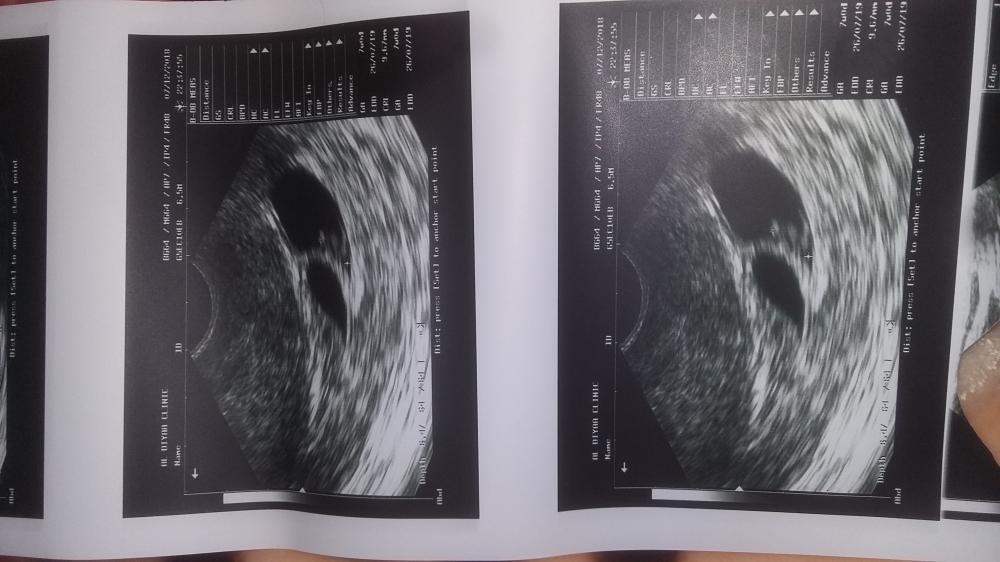

بنات يجيكم وسواس ان الجنين ميت ام لا ؟ مثلي ؟ قسم بالله مرات يجيني شعور كإن احد يقولي انتي مو حامل وان الجنين ميت من زمان وانتي ماتدرين عنه رغم اني احس بوحم بس الوسواس شغال ولي فتؤه مارحت المستشفى ابي اروح مره وحده على الشهر الرابع . ورحت بداية الشهر الثالث بالاسبوع التاسع

حاولت افهم بس ماقدرت شوفولي رامزي ويش يقول معي